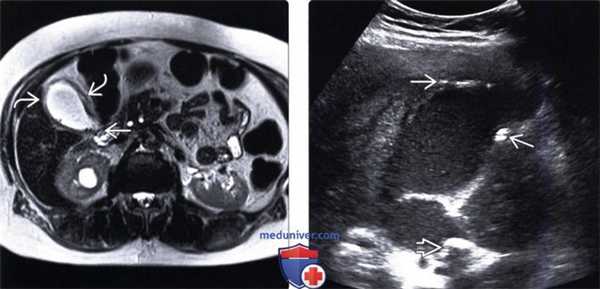

(Левый) При КТ с контрастным усилением у пациента с острым бескаменным холециститом визуализируются растянутый желчный пузырь с утолщенной стенкой, скопление перипузырной жидкости и воспаление перипузырной жировой клетчатки. Обратите внимание на слабое контрастирование стенки в области дна желчного пузыря.

(Правый) На поперечном УЗ срезе у пациента с бескаменным холециститом определяется сладж, утолщение стенки и чрескожный холецистостомический дренаж. Также видно скопление перипузырной жидкости.